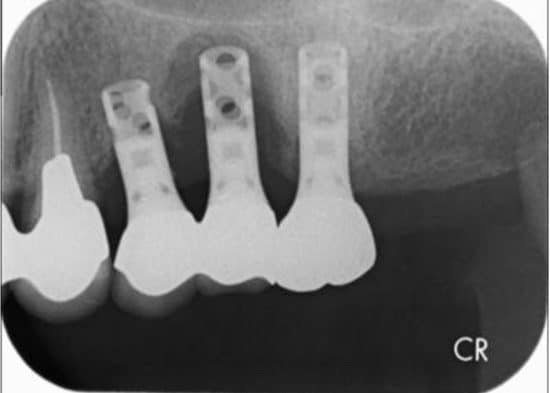

何年か前に入れたインプラントが揺れていると来院された患者さんがいました。レントゲン写真を撮ると、インプラントの周りが溶けて黒く写っています。